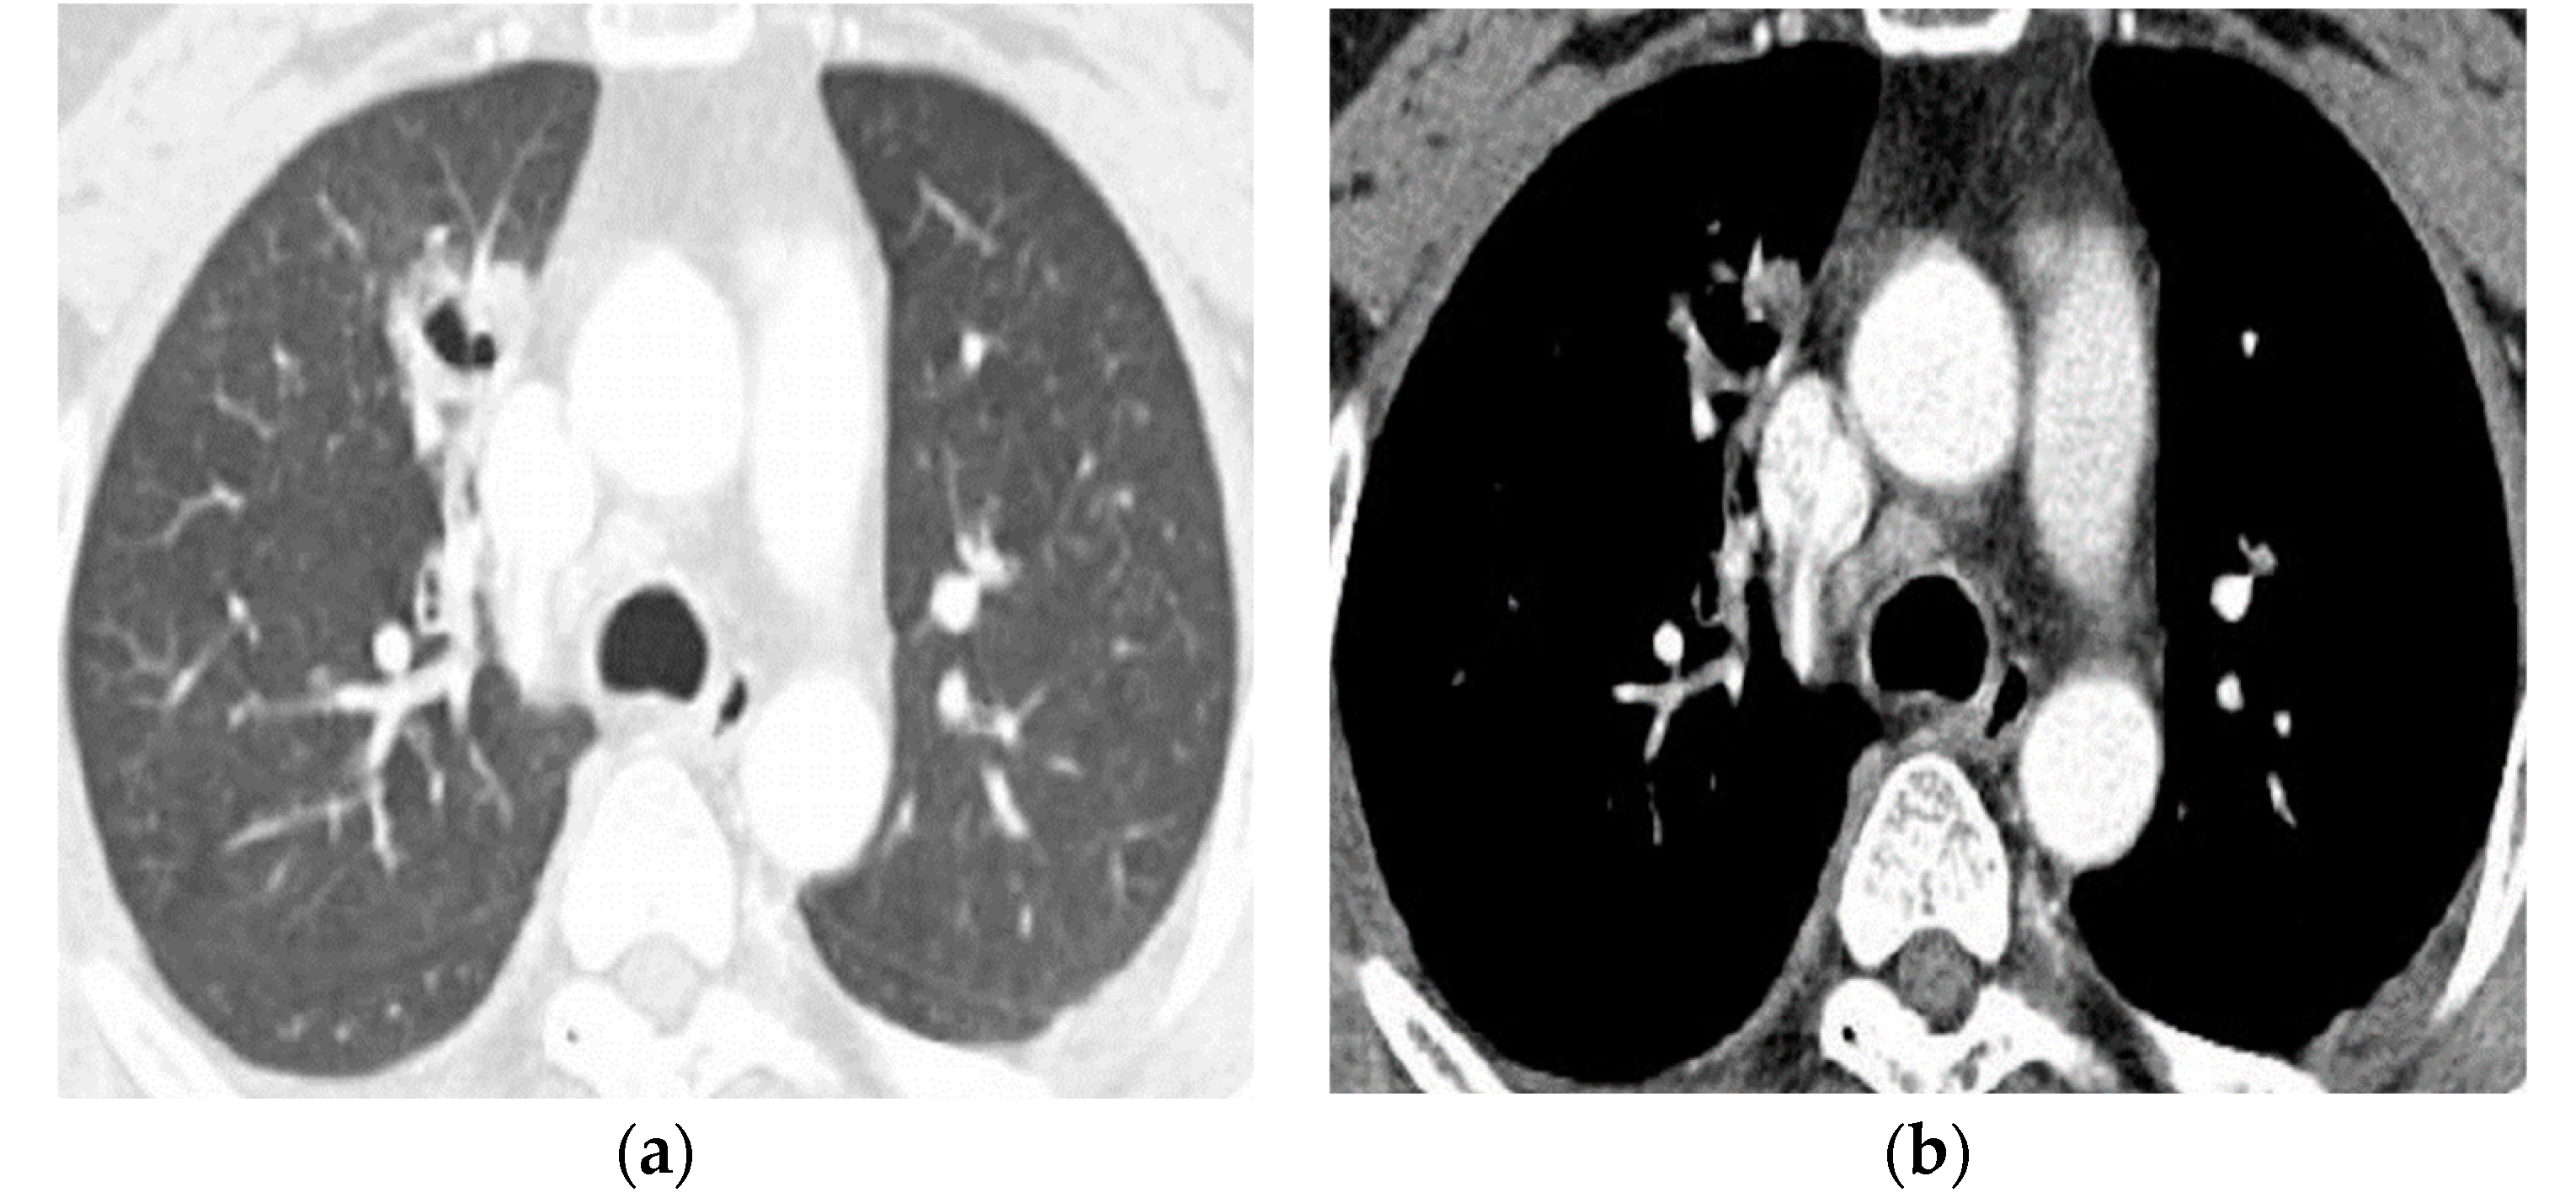

What Findings on Chest CTs Can Delay Diagnosis of Pleuropulmonary Paragonimiasis?

- Kim, T.S.; Han, J.; Shim, S.S.; Jeon, K.; Koh, W.-J.; Lee, I.; Lee, K.S.; Kwon, O.J. Pleuropulmonary paragonimiasis: CT findings in 31 patients. AJR. Am. J. Roentgenol. 2005, 185, 616–621. [Google Scholar] [CrossRef]

- Song, J.U.; Um, S.W.; Koh, W.J.; Suh, G.Y.; Chung, M.P.; Kim, H.; Kwon, O.J.; Jeon, K. Pulmonary paragonimiasis mimicking lung cancer in a tertiary referral centre in Korea. Int. J. Tuberc. Lung Dis. Off. J. Int. Union Against Tuberc. Lung Dis. 2011, 15, 674–679. [Google Scholar] [CrossRef] [PubMed]

- Shu, Q.-H.; Yang, Y.; Li, S.-D.; Zhao, J.-S.; Li, S.-H.; Wang, M.-M.; Wang, W.-Q.; Tian, M.; He, S.-M.-Q.; Ma, Z.-Q.; et al. Analysis of the misdiagnosis of 8 adult cases of paragonimiasis with lung masses as the main manifestation in Xishuangbanna, Yunnan. J. Cardiothorac. Surg. 2021, 16, 28. [Google Scholar] [CrossRef] [PubMed]